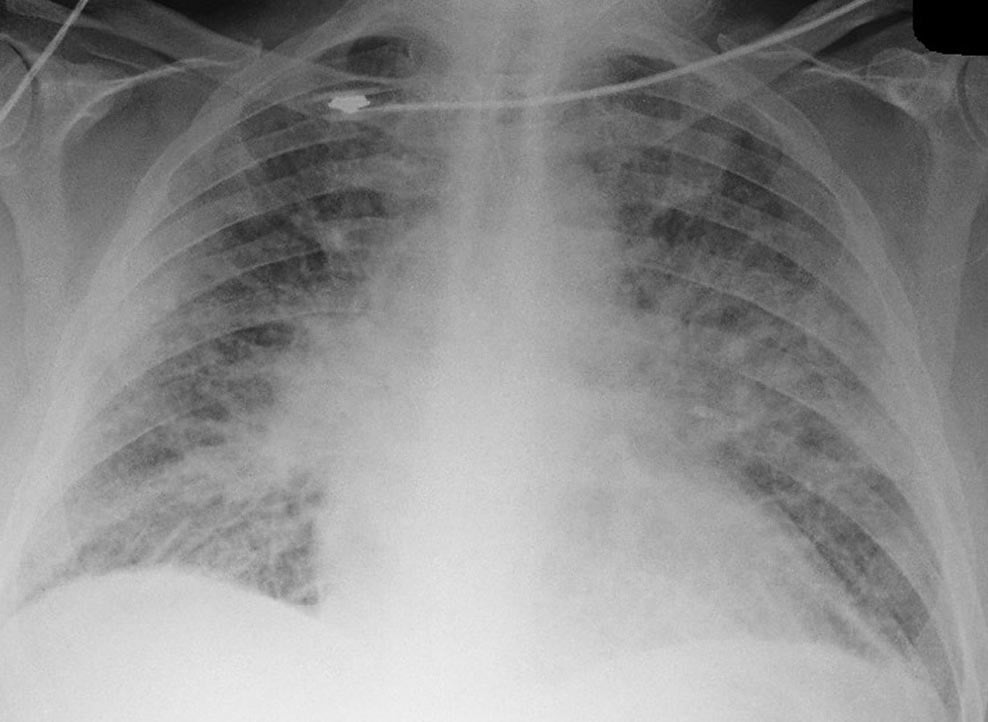

55 yo M presents to the Emergency Department with progressive shortness of breath and lightheadedness for one day. At arrival he is found to be hypotensive with signs of cardiogenic shock. EKG shows ST elevations in inferior leads. Learners should incorporate US as part of the assessment of this hypotensive patient and be able to resuscitate this patient in cardiogenic shock from underlying inferior MI.